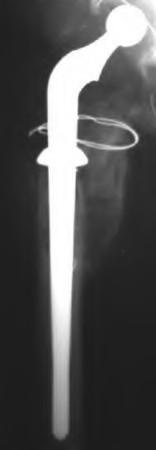

A 72-year-old male presents 2 years status post fixation of an impending pathologic right femur fracture due to metastatic renal cell carcinoma. He is minimally ambulatory due to pain. Despite radiation therapy, there has been progression of the lesion with extensive cortical bone loss, which is shown in Figure A. A proximal femoral replacement arthroplasty is performed without complications, and is demonstrated in Figure B. Which of the following is true regarding this patients post-operative course?

Deep prosthetic infection is the most common complication after hip arthroplasty performed for salvage of failed internal fixation after pathologic proximal femoral fracture secondary to malignancy.

Jacofsky et al reviewed the complications in 42 patients with a mean age of 63 who were treated with hip arthroplasty for salvage of failed treatment of a pathologic proximal femoral fracture. Multiple different constructs were used.

The most common complication was deep prosthetic infection, which occurred in nearly 10% of the patients studied. All infections occured in patients whom had previously received radiation. The mean Harris Hip score improved from 42 to 83 points post-operatively, and 41 of the 42 patients were ambulatory at follow-up. Implant survivorship free of revision for any reason at 5 years was 90%, and free of revision for aseptic failure or radiographic failure was 97%.

Figure A shows a lytic lesion of the proximal femur with an intramedullary implant. Figure B shows a proximal femoral replacement.